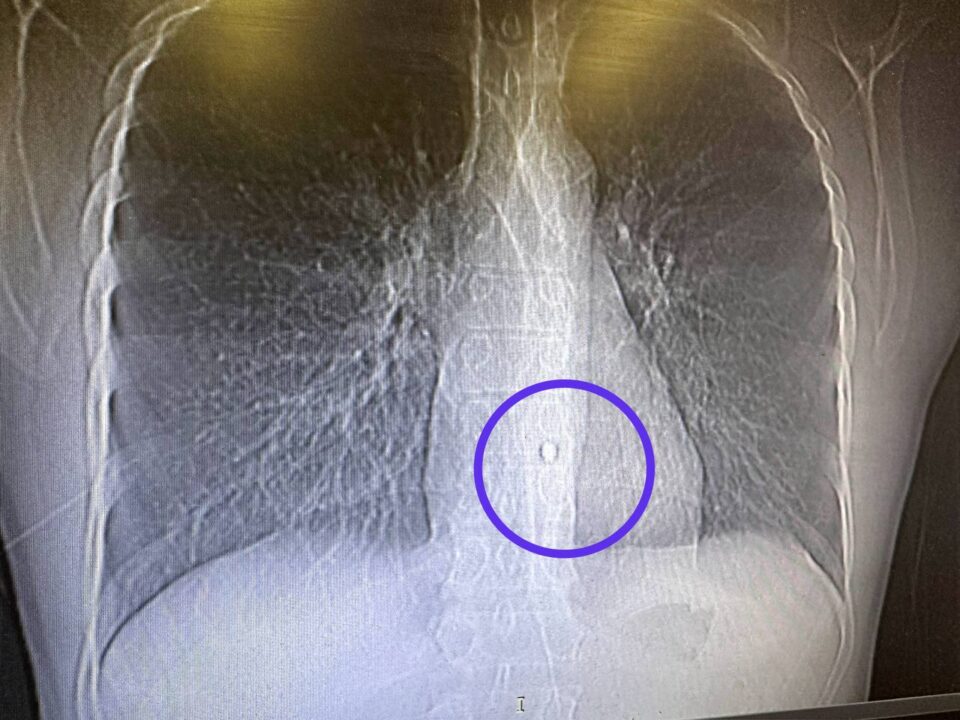

Так, 17 марта военнослужащий из Татарстана получил осколочное ранение левой половины грудной клетки с повреждением легкого, один из осколков попал в стенку аорты.

Команда торакальных хирургов и анестезиологов смогла извлечь осколок через проколы за 2,5 часа.